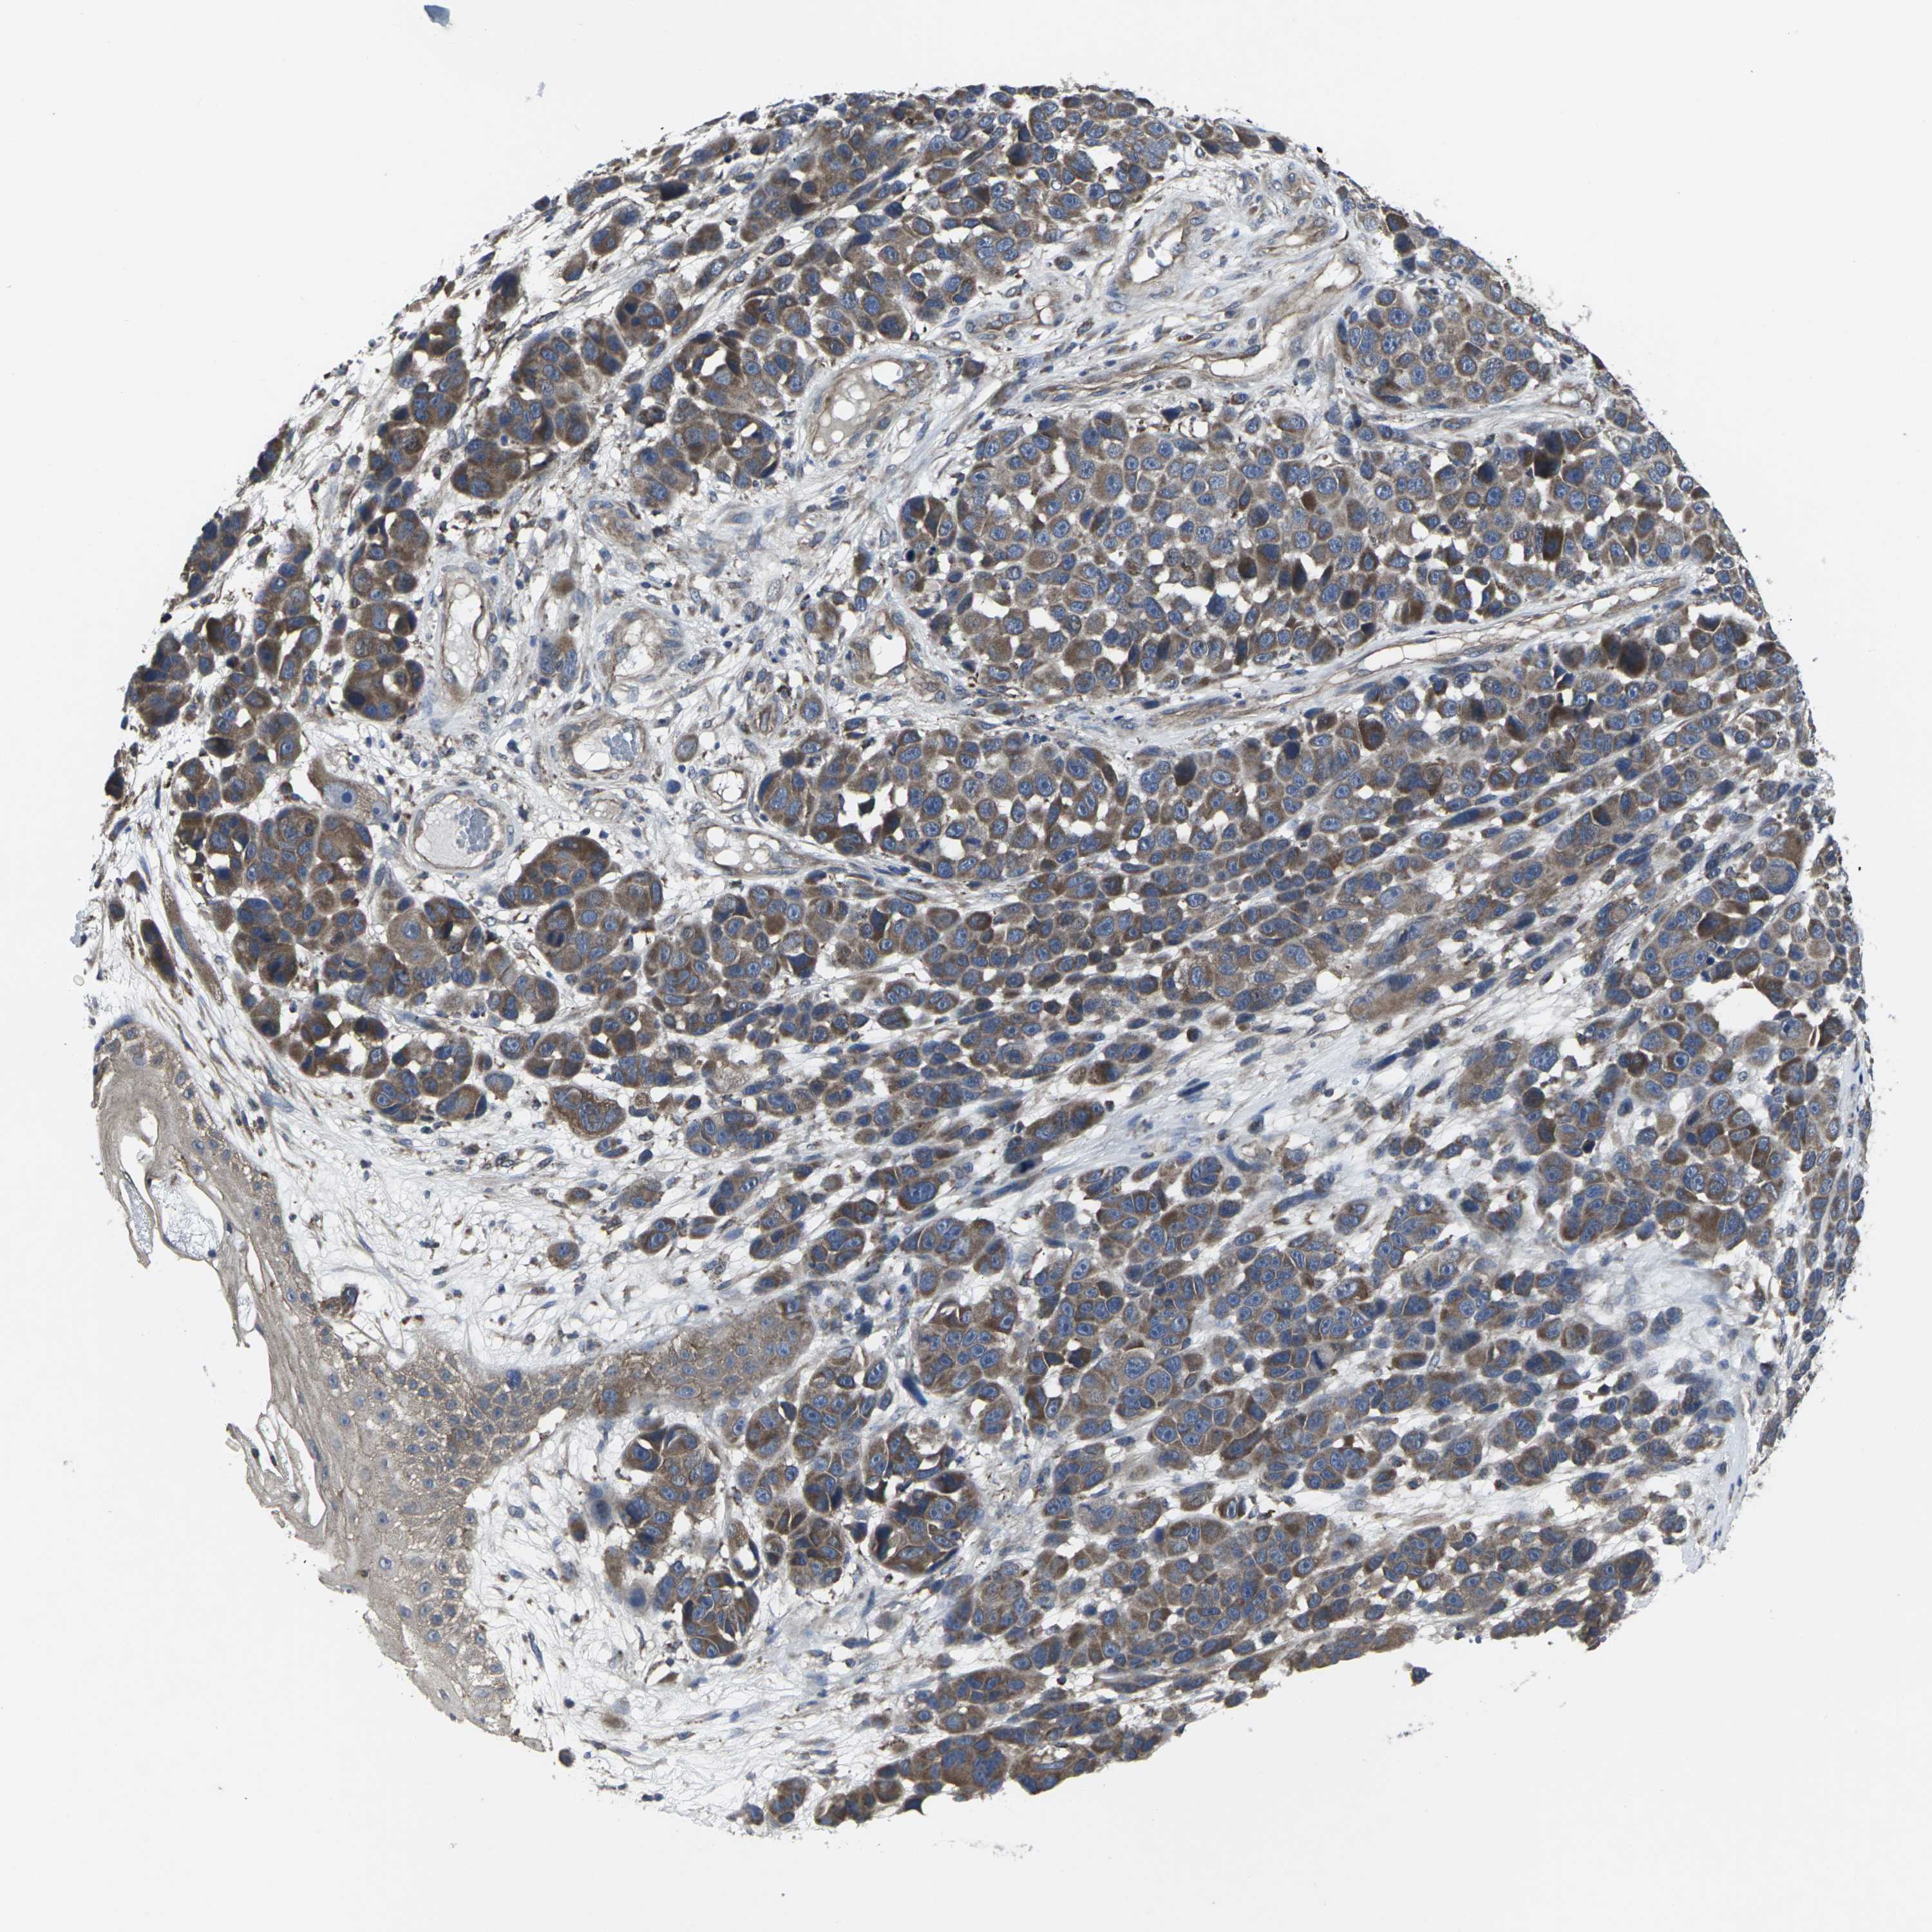

MELANOMA - Protein expressioni

A mouse-over function shows sample information and annotation data. Click on an image to view it in a full screen mode. Samples can be filtered based on level of antibody staining by selecting one or several of the following categories: high, medium, low and not detected. The assay and annotation is described here.

Note that samples used for immunohistochemistry by the Human Protein Atlas do not correspond to samples in the TCGA dataset.

Antibody stainingi

Antibody staining in the annotated cell types in the current human tissue is reported as not detected, low, medium, or high, based on conventional immunohistochemistry profiling in selected tissues. This score is based on the combination of the staining intensity and fraction of stained cells.

Each image is clickable and will lead to virtual microscopy that enables deeper exploration of all samples and also displays staining intensity scores, fraction scores and subcellular localization as well as patient and tissue information for each sample.

Antibody HPA063708

Antibody HPA064435

Antibody CAB010297

Staining

High

Medium

Low

Not detected

Intensity

Strong

Moderate

Weak

Negative

Quantity

>75%

75%-25%

<25%

None

Location

Nuclear

Cytoplasmic/membranous

Cytoplasmic/membranous,nuclear

Malignant melanoma, NOS

Malignant melanoma, Metastatic site